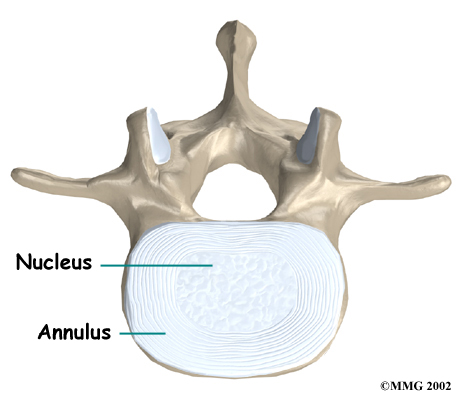

Intervertebral discs separate the vertebrae. The discs are made of connective tissue. Connective tissue is the material that holds the living cells of the body together. Most connective tissue is made of fibers of a material called collagen. These fibers help the disc withstand tension and pressure.

Intervertebral discs separate the vertebrae. The discs are made of connective tissue. Connective tissue is the material that holds the living cells of the body together. Most connective tissue is made of fibers of a material called collagen. These fibers help the disc withstand tension and pressure.

A disc is made of . The center, called the nucleus, is spongy. It provides most of the disc's ability to absorb shock. The nucleus is held in place by the annulus, a series of strong ligament rings surrounding it. Ligaments are connective tissues that attach bones to other bones.

Healthy discs work like shock absorbers to cushion the spine. They protect the spine against the daily pull of gravity. They also protect it during strenuous activities that put strong force on the spine, such as jumping, running, and lifting.